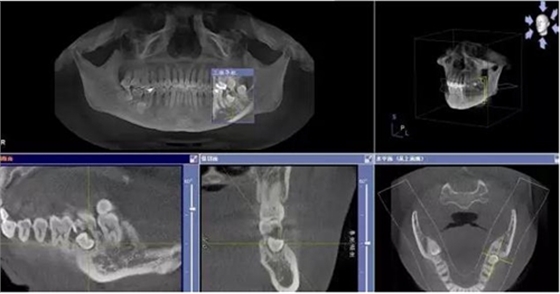

患者、申xx、女、40歲,主訴:左側(cè)下頜后牙牙齦紅腫不適數(shù)月。??茩z查:37合面有一開髓孔。髓腔內(nèi)有一暫封小棉球,探針髓腔底部出血,疑為在外院治療導致底穿。x線片檢查:37頰側(cè)齦下有一枚多生牙,多生牙壓迫頰側(cè)牙根及牙體組織大量吸收。

圖1.術(shù)前的CBCT檢查:37頰側(cè)部分牙根被完全壓迫吸收。